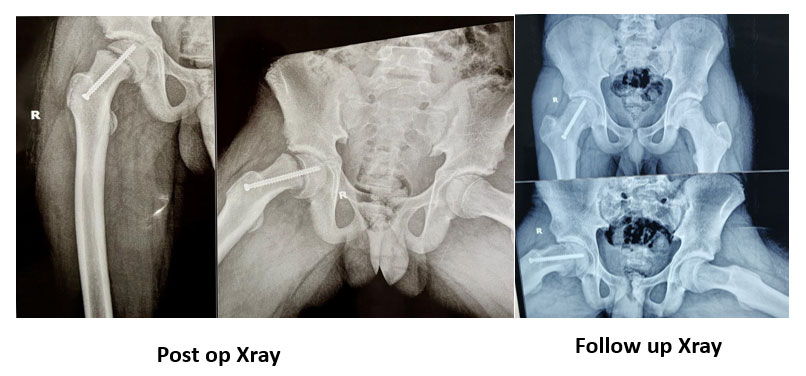

SCFE